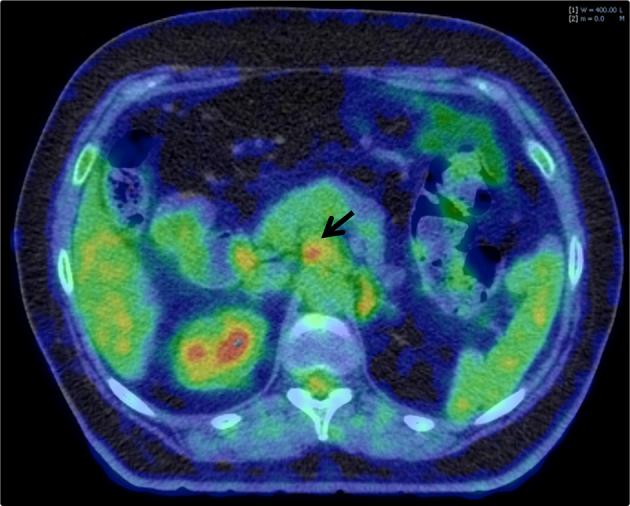

Functional imaging gives information about physiological heterogeneity in tumours. The utility of functional imaging tests in providing predictive and prognostic information after chemoradiotherapy for both oesophageal cancer and pancreatic cancer will be reviewed. The benefit of incorporating functional imaging into radiotherapy planning is also evaluated. In cancers of the upper gastrointestinal tract, the vast majority of functional imaging studies have used (18)F-fluorodeoxyglucose positron emission tomography (FDG-PET). Few studies in locally advanced pancreatic cancer have investigated the utility of functional imaging in risk-stratifying patients or aiding target volume definition. Certain themes from the oesophageal data emerge, including the need for a multiparametric assessment of functional images and the added value of response assessment rather than relying on single time point measures. The sensitivity and specificity of FDG-PET to predict treatment response and survival are not currently high enough to inform treatment decisions. This suggests that a multimodal, multiparametric approach may be required. FDG-PET improves target volume definition in oesophageal cancer by improving the accuracy of tumour length definition and by improving the nodal staging of patients. The ideal functional imaging test would accurately identify patients who are unlikely to achieve a pathological complete response after chemoradiotherapy and would aid the delineation of a biological target volume that could be used for treatment intensification. The current limitations of published studies prevent integrating imaging-derived parameters into decision making on an individual patient basis. These limitations should inform future trial design in oesophageal and pancreatic cancers.

功能成像可提供有关肿瘤生理异质性的信息。本文将综述功能成像检查在食管癌和胰腺癌放化疗后提供预测和预后信息方面的效用。同时也评估将功能成像纳入放疗计划的益处。在上消化道癌症中,绝大多数功能成像研究都使用了(18)F-氟脱氧葡萄糖正电子发射断层扫描(FDG-PET)。在局部晚期胰腺癌中,很少有研究探讨功能成像在对患者进行风险分层或辅助靶区定义方面的效用。从食管癌数据中出现了某些主题,包括对功能图像进行多参数评估的必要性以及反应评估的附加价值,而不是依赖单一时间点的测量。目前,FDG-PET预测治疗反应和生存的敏感性和特异性还不够高,无法为治疗决策提供依据。这表明可能需要一种多模态、多参数的方法。FDG-PET通过提高肿瘤长度定义的准确性和改善患者的淋巴结分期,改善了食管癌的靶区定义。理想的功能成像检查应能准确识别放化疗后不太可能实现病理完全缓解的患者,并有助于勾勒出可用于强化治疗的生物靶区。已发表研究的当前局限性阻碍了将成像衍生参数纳入个体患者的决策制定。这些局限性应为未来食管癌和胰腺癌的试验设计提供参考。